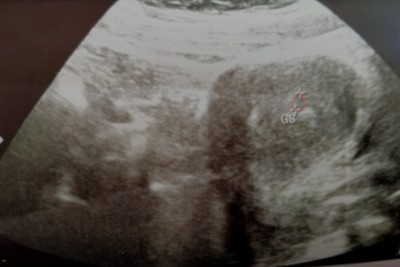

Keseyi görüyor musunuz kızlar var mı birsey

Ultrasondan kaynaklı biraz kötü ultrason cihazı yani. Doktorun ölçüm yapmış işaretlemiş

Ultrason cihazından kaynaklı canım devlete gidiyosun herhalde benimde aldığım bütün ultrason görüntüleri böyle

2tane + var orda işaretlenmiş yani

Canım normalde bu şekilde karanlık olur ama tam netlestirememis demek ki cihaz. Benim doktorum da çok uğraştı keseyi netleştirmek için.

İlk muayenede 4+3 du bugün 6+2 ama kese o halde işte

Al canim ben sana işaretledim kirmizi cizgi ile kesen o senin ama daha cok kucuk kac haftaliksin. 3 4 filan mi?

Hm biraz kucuk kalmış olabilir o zaman kese o yuzden oyle demiştir. Bekleyin bir dahaki kontrole kadar büyümesi lazim. Ama bir sey sormak istiyorum. Regline gore mi 5 haftaliksin ultrasonda da 5 mi çıktı.

Son âdet tarihine göre ama hani kese büyümemis dedi ya acaba büyür mü gelişir mı

Belki gec dollenmedir canim ultrasonda da 5 dedi ise bilemedim ama bekle canim her şeyin hayırlısı.

Ultrason cihazı kötü sanırım ama Ölçmüş orda iki artı arasında canım çok minnak daha görürsün iki hafta sonra git.Sonrada bu noktaydı şimdi sığmıyor içime diye oturur gülersin :)) Allah sağlık versin inşallah.